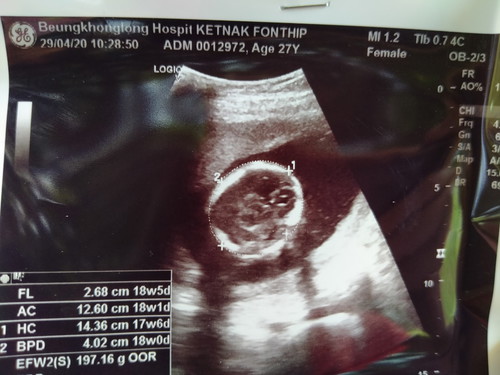

อันตร้าซาว ที่หมอให้ 18w. นี้คือตรงใช่ไหมคะ

พอดีนับกับหมอ บอกประจำเดือนขาดครั้งสุดท้ายตอนไหน ได้ 19 w ตกลงคือยังไงคะ เชื่ออันไหนคะ มีคุณแม่ท่านไหนไม่ตรงบ้างคะ ขอข้อมูลหน่อยคะ กังวลคะ น้ำหนักน้องคะ

อ่านเพิ่มเติมของบ้านนี้หมอบอกว่า จะอยู่ในเกณฑ์+- ไม่เกิน1สัปดาห์ค่ะ หมอจะวัดขนาดกะโหลกศรีษะ กระเพาะอาหาร และอวัยวะต่างๆของร่างกายน้อง พอครบทุกส่วน จะมีค่าเฉลี่ยว่าตอนนี้เราท้องประมาณกี่สัปดาห์ ความคาดเคลื่อน บวก-ลบประมาณ1สัปดาห์ ค่ะ ดูจากใบก็ปกตินะคะ

ไม่ต้องกังวลค่ะ ห่างกันเเค่ไม่กี่วันเองจ้า ซาวด์รอบเเรกเชื่อได้ค่ะ ซาวด์บอก18วีค5วัน รอบประจำเดือนบอก19วีค ห่างกันเเค่1วัน ไม่ต้องกังวลขนาดนั้นจ้า